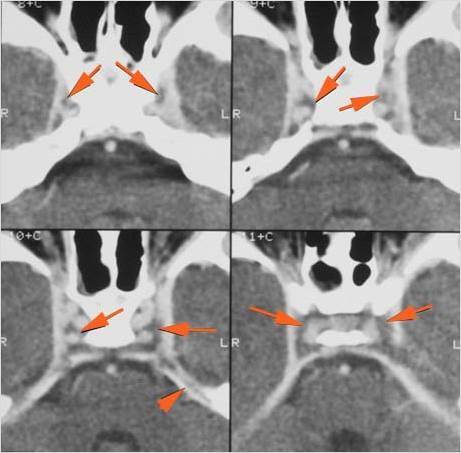

Orbits

The extraconal orbital fat is abnormal.

There is a subperiosteal abscess or edema along the medial wall, roof or floor of the orbit.

The extraocular muscles are swollen or otherwise abnormal.

There is bone erosion along the walls of the orbit.

The superior and/or inferior ophthalmic veins are dilated or thrombosed.

Intracranial

There is a subperiosteal fluid collection or abscess along the boney walls of the anterior or middle cranial fossa.

There is an epidural fluid collection or abscess along the boney walls of the anterior or middle cranial fossa.

There is a subdural fluid collection or abscess along the boney walls of the anterior or middle cranial fossa.

There is a subdural fluid collection or abscess along the falx cerebri or within the tentorium.

There is evidence of thrombus, thrombophlebitis or other occlusive or inflammatory process of the cavernous sinus.